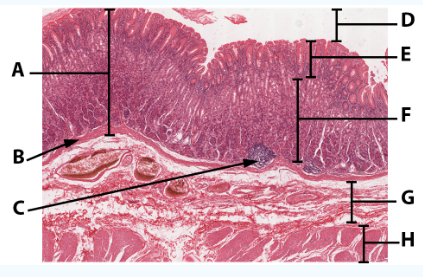

A

Muscularis

B

Submucosa

C

Mucosa

D

Muscularis mucosa

E

lamina propria

F

stratified squamous epithelial tissue

area

Esophagus